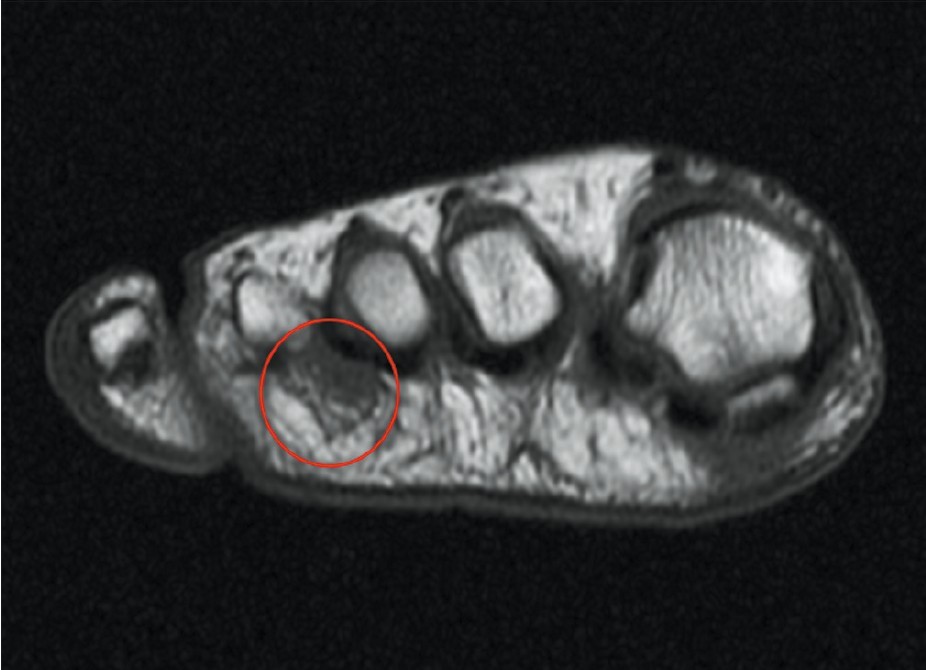

종골과 중족골 피로 골절이 발에 있어서 가장 흔한 피로 골절(stress fracutres)의 부위에 해당한다. T1 강조 영상에서는 골절의 부종과 혈종이 정상적인 높은 신호의 골수를 가로지르는 낮은 신호의 띠 형태로 나타난다. 지방 억제 T2 강조 또는 STIR 영상은 골절 부위의 증가된 신호 강도를 보여준다. (그림 47-2)

△ 그림 47-2. A. 전족부의 T1 강조 축면 영상이 두번째 중족골의 피로골절을 보여준다.

B. 관상면 지방 억제 T2 강조 영상은 연부조직과 피로골절로 인한 골수종의 윤곽을 보여준다.